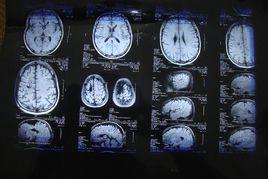

各種破壞性病變均可造成腦組織壞死軟化,腦脊液充填,形成囊性軟化灶。常見原因包括腦出血、腦梗塞、腦炎和腦外傷。

腦因腦組織需氧極高,一旦動脈受阻必然導致供應區域的軟化,腦軟化亦即其他器官的梗死.大者為軟化,小者為腔隙,多數腔隙稱腔隙狀態.引起軟化及腔隙狀態的原因有栓塞,動脈血栓形成,動脈痙攣,循環功能不全等病因.軟化可分為貧血性及出血性兩種,動脈阻塞可造成貧血性軟化,亦可以為出血性軟化,而靜脈阻塞則幾乎完全為出血性軟化.貧血性軟化的病變過程大體上可分為三期:壞死期,軟化期,修復期.軟化區內的細胞已壞死,缺血性半暗帶(半月區)的細胞調亡或凋亡前狀態,功能低下,可出現神經系統和運動系統功能障礙.